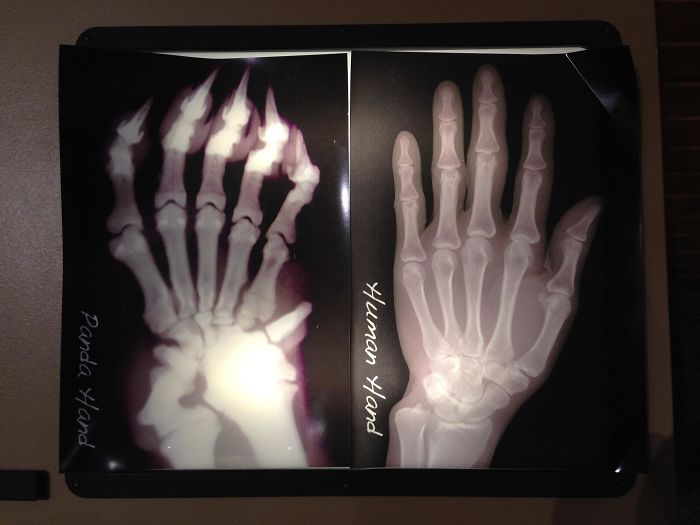

X-Ray Of A Panda Hand vs. A Human Hand; Pandas Have An Extra "Thumb" To Help Grip Bamboo Stalks